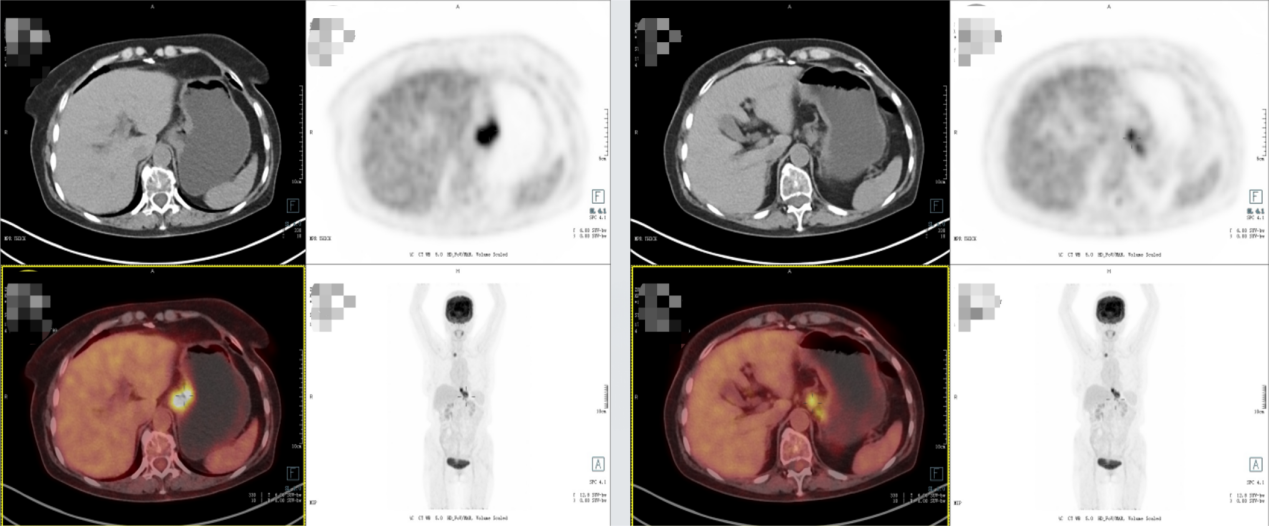

PET-CT:食管下段至贲门部软组织灶伴FDG代谢增高,考虑贲门癌累及食管下段。右侧胸廓入口处气管旁、贲门旁淋巴结转移。

2025年7月16日复查影像学显示,贲门癌化疗后,贲门胃壁稍增厚;双肺间质性改变。

2025年11月19日复查影像学显示,贲门癌化疗后,贲门胃壁稍增厚;贲门部肿物及转移淋巴结较前明显退缩,影像表现为接近CR(无可评价病灶)。